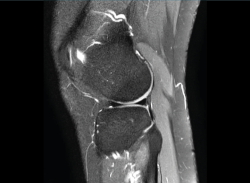

1.1. Meniscos

Figura 30. Corte de secuencia sagital T2 Fat-Sat de resonancia magnética de rodilla: menisco externo normal.

Se identifican como estructuras hipointensas en todas las secuencias, con asta anterior y posterior de morfología triangular.

Figura 31. Corte de secuencia sagital T2 Fat-Sat de resonancia magnética de rodilla: menisco interno normal.

La RM es la técnica de elección en el diagnóstico de la patología meniscal(17)(Figuras 30, 31, 32, 33, 34 y 35).